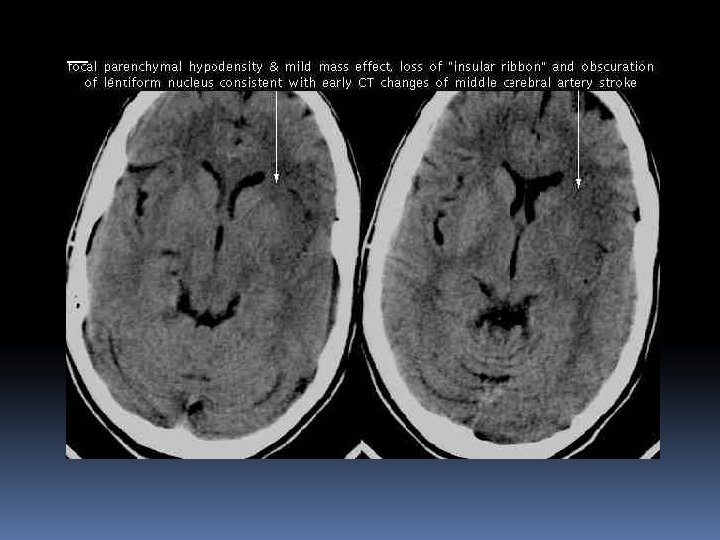

Acute Ischemic Stroke Work Up Labs: CBC with platelets, CMP, PTT, cardiac biomarkers, EKG. Imaging: Emergent non-contrast CT Distinguishes hemorrhagic from ischemic stroke Defines age and anatomic distribution of stroke Large hypodense area seen within 3 hours brings into question of timing of AIS and may predict poor outcome Hyperdense MCA sign, insular ribbon sign, obscuration of lentiform nucleus, loss of gray-white junction

Large Cortical Hypodensity